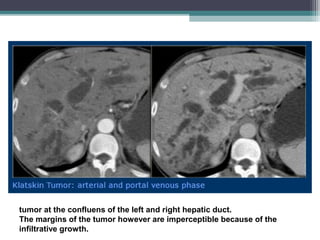

• CT :

• Tumour might appear hypodense to liver in both unenhanced and Enhanced

images , But Focally thickened bile duct wall due to infiltrating tumour may

appear hyperdense to the liver in the arterial and portal venous phase .

Delayed enhancement can be seen in 8-15 min post Contrast injection.

tumor at the confluens of the left and right hepatic duct.

The margins of the tumor however are imperceptible because of the

infiltrative growth.